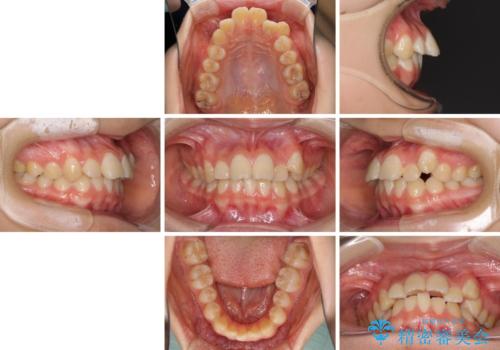

目立つ八重歯を治したい インビザラインによる矯正治療

- 目立つ八重歯を改善したいとのことで来院された患者様です。

奥歯の咬み合わせは左右とも理想的なものでしたが、下顎前歯が1本欠損しているため、上下のバランスを保つことが難しい歯列でした。

唇を閉じたときに上顎前歯が下顎の唇に乗っかる印象があったため、八重歯の後方にある小臼歯を1本抜歯することとしました。

変則的な抜歯となるため、臼歯の咬合が理想的でなくなることが懸念されますが、インビザラインにて矯正治療を行うこととしました。

まずは補助装置を用いて八重歯を改善し、インビザラインにて歯列を整えましたが、当初の懸念が的中し、臼歯部の咬合を安定させることができませんでした。

海外留学の予定もあったため、後半は上下ワイヤー装置にて矯正治療を継続し、違和感なく咬合させることとなりました。